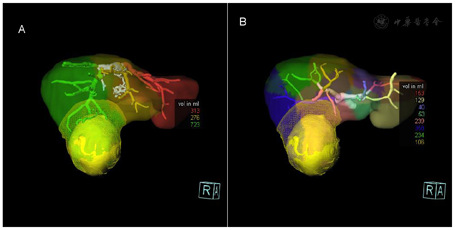

三维容积分析RECIST肝脏总容积1311.68ml,左叶体积约374.8ml,右叶体积约936.81ml;病灶直径76.28mm,最大正交直径74.63mm,容积243.31ml,虚拟手术2cm安全距离内容积约:337ml(虚拟手术切除容积),2cm安全距离外容积约:975ml(虚拟手术剩余肝容积)。

我国肝癌发病率高,呈逐年上升的趋势,病死率居恶性肿瘤第二位[1]。肝切除术是肝癌最主要的治疗手段。精细的术前评估和合理的手术规划,在保证彻底切除肿瘤的同时尽可能保存残余肝脏体积和功能,可以减少手术并发症,延长患者生存期。肝脏肿瘤三维可视化是指用于显示、描述和解释肝脏肿瘤三维解剖和形态特征的一种影像学工具。以SOMATOM Definition Flash机器采集的原始数据为基础,采用三维可视化软件重建的图像,可单独或联合显示肿瘤、全肝、肝动脉、肝静脉及门静脉的解剖关系及变异情况,确定拟切除的肝脏范围及受累需要重建的血管,对肿瘤体积及剩余肝脏体积进行精准定量,指导临床医生选择合适的手术方式,提高手术的精准性和安全性[2]。图像立体直观,且符合个性化需求,并可永久性存储重建后的图像,对手术方式的选择及术后随访有重要意义。